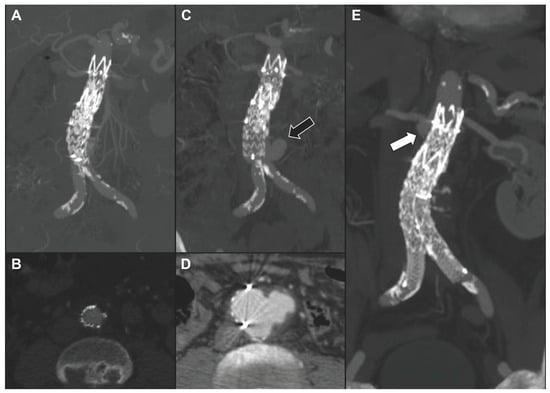

| 7 | M | 78 | Spondylodiscitis | Staphylococcus aureus | No | Symptomatic multi-lobular type IV TAAA | Oxacyllin | BEVAR | Alive | 36 | Stability | - |

| 8 | M | 72 | Sepsis in pre-existing TAAA | Escherichia coli | Yes | Symptomatic saccular type IV TAAA ± peri-aortic gas | Amoxicillin ± Clavulanate | BEVAR | Alive | 11 | Stability ± non-contiguous new arch lesion | TEVAR |